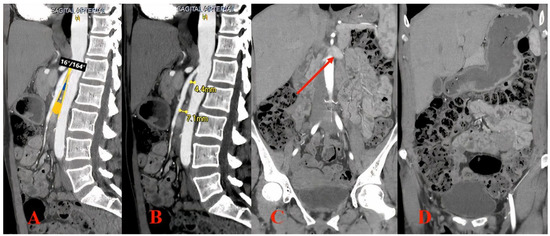

2. Imaging Diagnosis

3.1. Case Report

3.2. Stent Migration